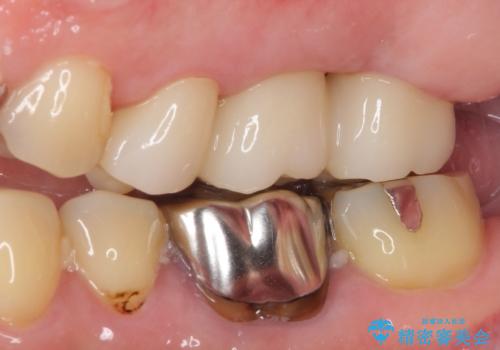

- 長い間虫歯を放置しており、違和感を感じ始めてきたので治療を開始したいと来院された患者様です。

極力抜歯が回避する方法を選択して診察を開始しましたが、1本は保存困難と判断されたため、フルジルコニアブリッジによる補綴治療を行うこととしました。

違和感を感じていた歯は虫歯が非常に大きく、骨に到達するほどの穴が空いていました。

抜歯をしたことで違和感はなくなり、ブリッジを装着したことでしっかりと噛めるようになり、患者様には大変満足していただきました。